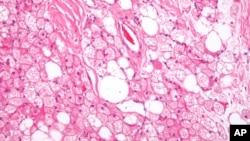

FILE - Brown fat cells are seen in the body.

Not all fat is bad. A new study has found that fat cells that lie beneath the skin’s surface may protect against bacterial infections.

U.S. researchers say dermal fat cells, known as adipocytes, produce peptides or proteins that shield against invading bacteria.

Experts explain adipocytes provide immediate defense against bacteria by producing antimicrobials, giving immune system white cells time to reach a wound site.